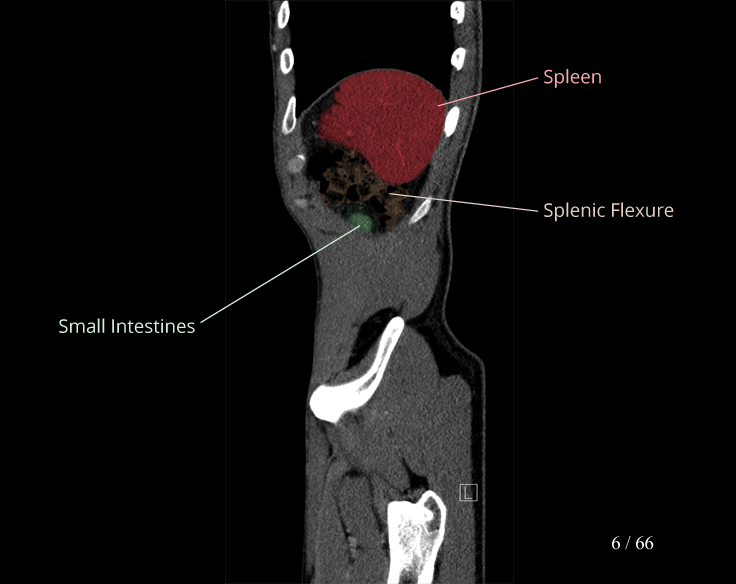

Body

Covers abdominal CT anatomy.